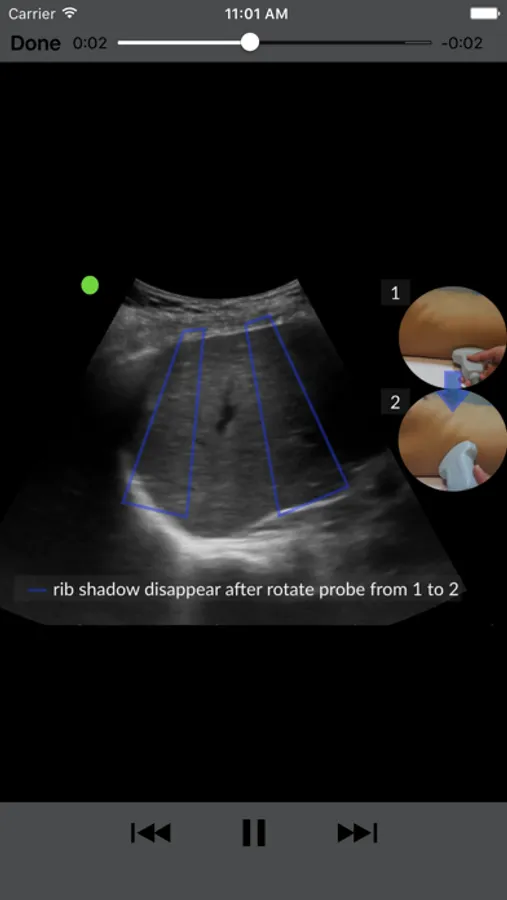

Lung: Basic A-E lines break down to pathology findings in prominent lung diseases